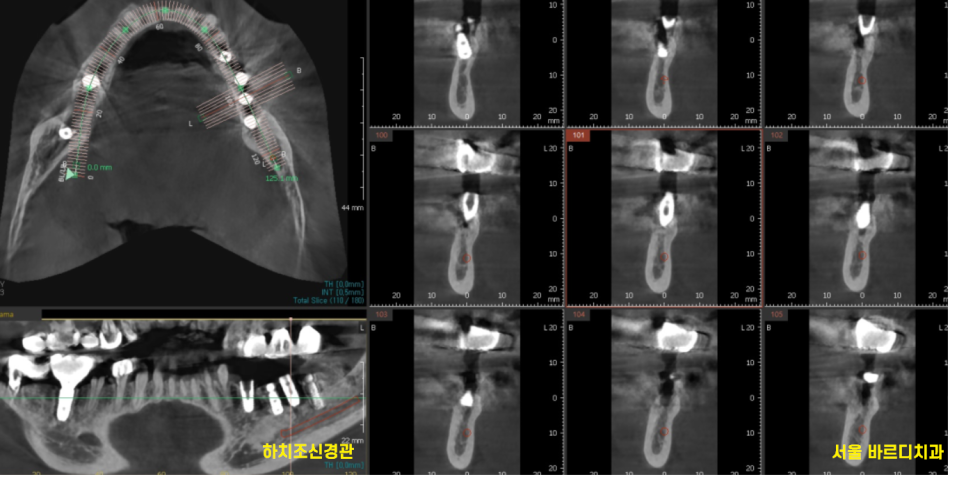

덕분에 치료에 동의해 주셔서

ct를 통해 디지털 분석 후

임플란트 수술까지 진행했습니다.